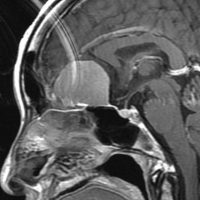

大脳鎌テント接合部髄膜腫 falcotentorial meningioma

30代の女性に発生した髄膜腫です,一見すると松果体細胞腫と見分けはつきません。右の画像に見られるように典型的な中脳水道狭窄を生じていました。

軽度の閉塞性水頭症もありますが,頭痛も無く無症状なので経過を観察しました。髄膜腫だと診断できるのは,右の画像で見られるようにガレン大静脈が右側に偏っているからです。松果体細胞腫の場合は,ガレン大静脈は上方に変位します。

1年間経過観察したら水頭症が進行して脳室が拡大,腫瘍のサイズも大きくなりました。右側の画像で見られるようにガレン大静脈の左側のテントの下面から発生した髄膜腫でした。

左は手術直後の画像です,手術は左側のテント下面を見るために,後頭部経テント法 OTA occipital transtentorial approach で,小脳テントの左側を切断して腫瘍を全摘出しました。右側は6年後の画像ですが,腫瘍再発はありません。

「注意」症状のない患者さんには,なかなか勧められないリスクの高い手術です。この患者さんの場合は無症状で水頭症も軽度で経過観察をしたのですが,本当はそうしてはならないものでした。閉塞性水頭症が急激に悪化して,急性水頭症のために意識障害になる可能性があるものです。